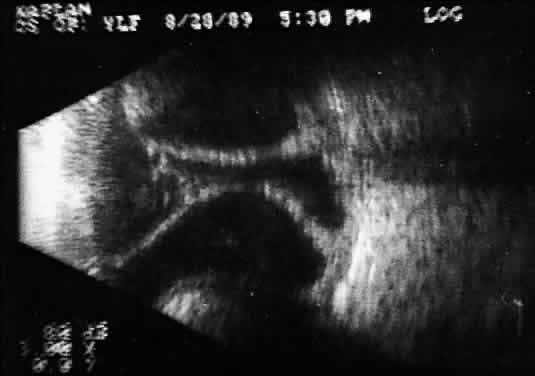

Recent improvements in computer technology and digital B-scan devices have permitted the development of tomographic (3D) static displays. The new devices, often called 3D ultrasound instruments, increase understanding of complex topographic information (Fig. 18). Sophisticated software permits measurements of captured images (linear, area, and volume) as well as surface renderings18,19 (Figs. 19 and 20). Kinetic (real-time) information is not yet available in 3D and continues to be obtained during kinetic B-scan examinations performed before 3D image capture.

Fig. 18. 3D tomographic ultrasonogram software permits a combined tomographic 3D coronal/sagittal view of extensive choroidal detachment involving the anterior and postequatorial regions of the eye.